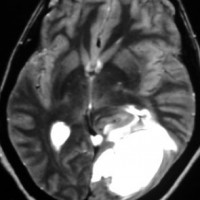

画像と病理所見4

40代男性の大脳鎌テント接合部の硬膜に発生したグレード3です。激しい出血のために腫瘍摘出を部分摘出で中断せざるを得なかった例です。

この例でも,硬膜発生腫瘍ということは手術前の画像診断で解ってはいたのですが,髄膜腫と異なり不整な形をしてのう胞があり,一部は腫瘍壊死でした。

上の2例は,髄膜腫とは違うと一見してわかる,典型的なSFT/ヘマンジオペリサイトーマの例ですが,髄膜腫と鑑別できないようなものの方が多いです。